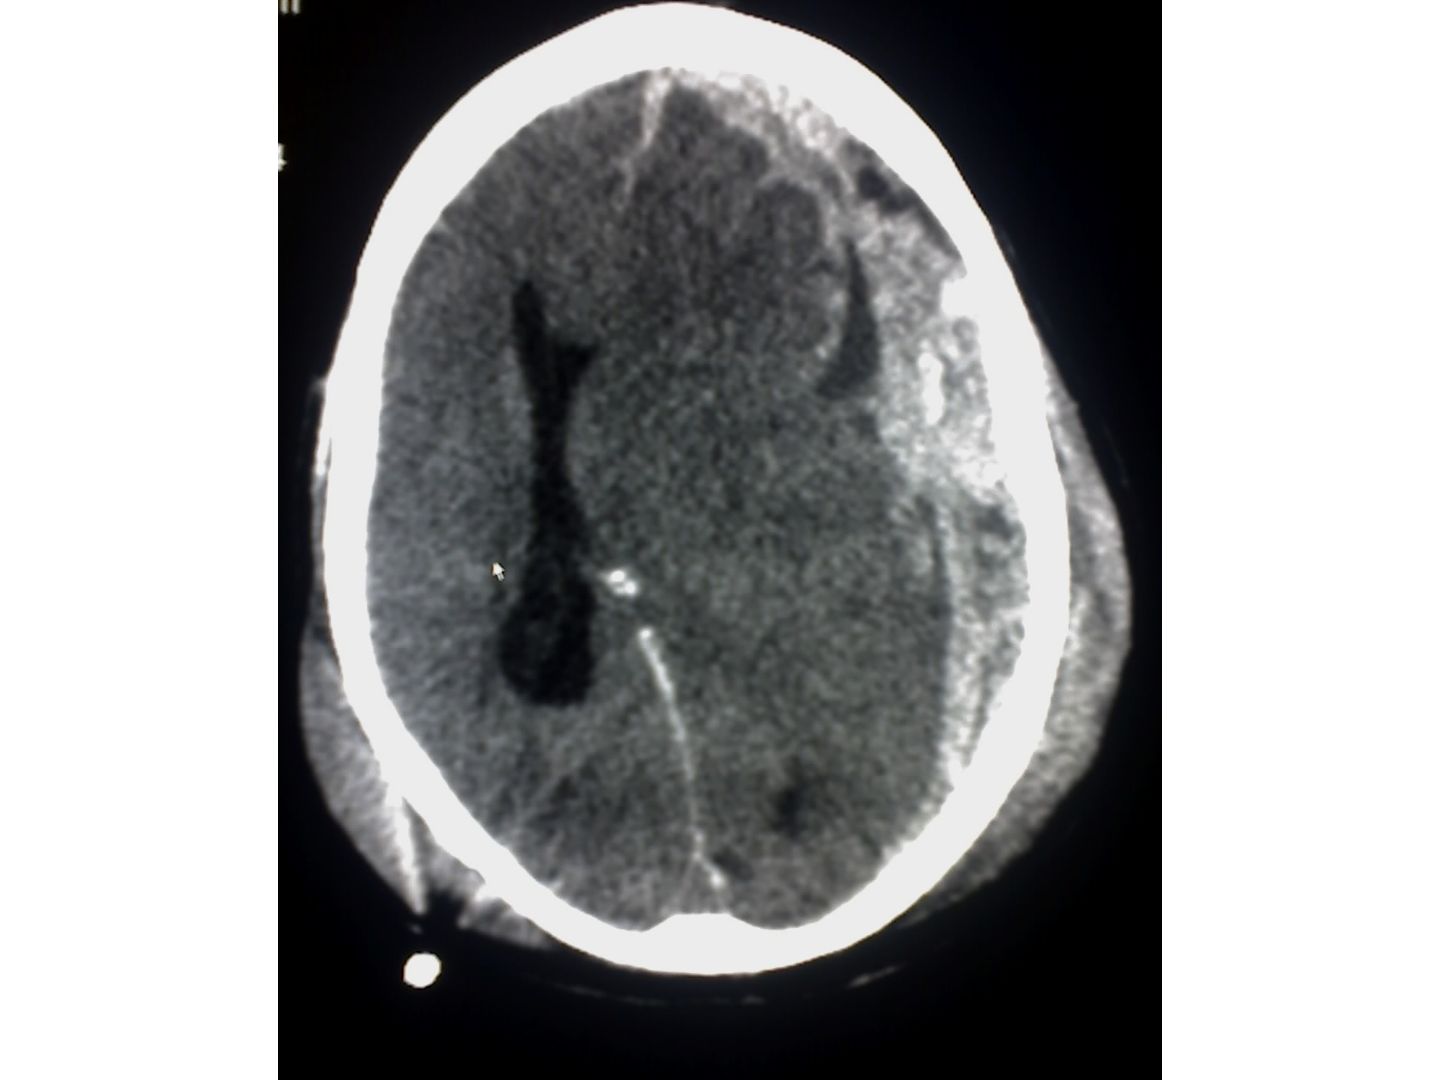

Computertomografische Aufnahme (CCT) mit sichelförmiger, konvex-konkaver Blutansammlung zwischen Dura mater und Arachnoidea. Typisch für eine subdurale Blutung (häufig traumatisch bedingt).

CTT: Subdurales Hämatom - Computertomografische Aufnahme (CCT) mit sichelförmiger, konvex-konkaver Blutansammlung zwischen Dura mater und Arachnoidea. Typisch für eine subdurale Blutung (häufig traumatisch bedingt).